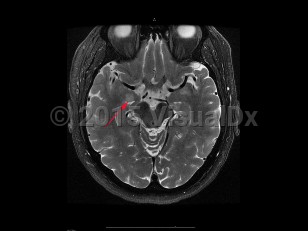

To distinguish encephalitis from other causes of encephalopathy, core components of the presentation of encephalitis include the presence of fever (within 72 hours before or after presentation), cerebrospinal fluid (CSF) pleocytosis (≥ 5 /mm3), or MRI or electroencephalogram (EEG) changes consistent with encephalitis.